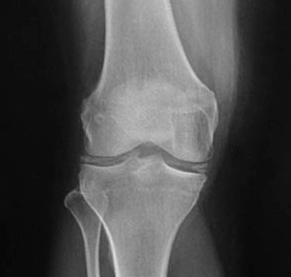

The inflammatory arthritis seen on this knee film.

What is CPPD (or pseudogout)